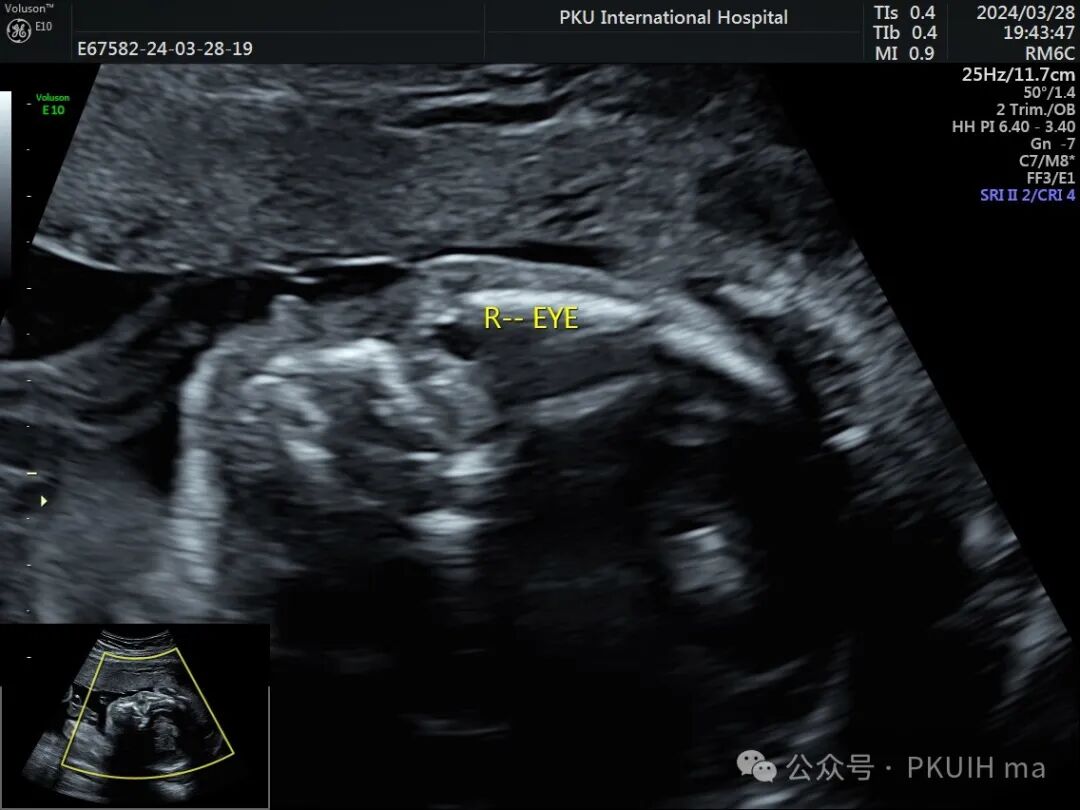

这个胎儿的眼睛怎么了?

今天来看一个胎儿,在大排畸检查时发现

右眼框、右眼球发育小,晶状体发育也很小

右眼晶状体后方见高回声区,其内未探及血流信号

双眼球对比观察两眼球发育不对称,右眼明显发育小

右眼球情况:两个手标分别代表晶状体和后方的永存玻璃体

实时动态观察双眼发育不对称,右眼小;两侧眼球内晶状体、玻璃体均可见,右侧晶状体小,晶状体后缘玻璃体内见不规则的高回声区。